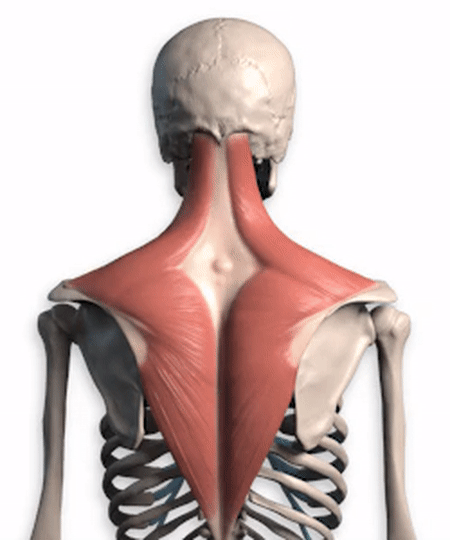

私の友人の多くはこう考えている。首は首、肩は肩、背中は背中。医学生からすれば、この考え方は偏っている。颈、肩、背1つの筋肉だけから、1つのものとして見て、その筋肉について簡単な分析をする。僧帽筋。

よく見るとこの僧帽筋。含む頭蓋底、首、肩、背中両側の僧帽筋は密接に連結し、菱形構造を形成している。背中の安定化首、肩、背中の様々な活動を達成するために非常に重要な役割を果たしている。僧帽筋は上部、中部、下部のバンドルに分かれており、収縮する部位によって異なる動きを完成させる。。